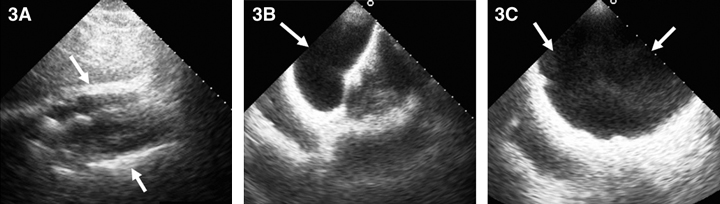

On the GHPS (Figure 1) a radiolucent pericardial halo was apparent, raising concerns for pericardial effusion. The rest of the study was unremarkable, with normal regional wall motion and quantitative ejection fraction of the cardiac ventricles. Comparison with a recent chest x-ray (Figure 2) revealed radiolucency external to the chest wall. Subsequent transthoracic echocardiography (Figure 3) ruled out the presence of pericardial effusion.

3: Two-dimensional echocardiogram. 3A: Subcostal views showing pericardial border anteriorly and posteriorly (arrows) without evidence of pericardial effusion. 3B: Subcostal view with the transducer directed anteriorly to image the saline-filled breast implant (arrow). 3C: Anterior chest wall imaging depicting the implant (arrows). |